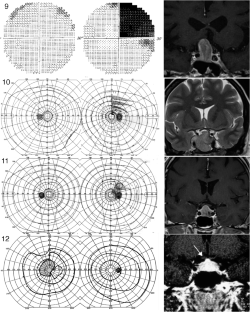

The hemi-decussation at the optic chiasm creates the potential for crossed and uncrossed fibers to be affected in isolation or in various combinations of nerve, chiasm and tract, with patterns that reflect the retinotopic arrangement of axons. We present seventeen cases that illustrate the field defects that can result and review the literature to create a taxonomy of junctional visual field defects. The complete junction defect is blindness in one eye and loss of the entire temporal field of the other. The classic junctional scotoma combines optic neuropathy in one eye with upper temporal hemifield loss in the other, and is often a sign of ventral compression. The less frequent atypical junctional scotoma involves the lower temporal hemifield and has a higher frequency of dorsal compression or non-compressive pathology. There are the monocular defects in the temporal (‘junctional scotoma of Traquair’) or nasal hemifield, the latter of which is rarely if ever due to a pituitary adenoma. Highly asymmetric bitemporal defects with or without a central scotoma and the paradoxical junctional scotoma occur by extension of the lesion causing the junctional scotoma of Traquair. The posterior junction defect results from combined damage to the optic chiasm and optic tract. Recognizing these various patterns is important clinically as junctional defects have the same localizing significance as bitemporal defects and are being encountered more often. In addition the probability of certain types of pathology varies with the type of junctional defect.

Figures in cases 1, 6 and 12 are adapted with permission from: Barton JJS, Benatar M. Field of Vision: a manual and atlas of perimetry, Humana Press (now Springer Nature), Totowa NJ, 2003, and those of cases 7, 9 and 15 are reproduced with permission from www.neuro-ophthalmology.ca. We thank Briar Sexton for sharing case 9 with us.

Barton, J.J.S., Özturan, G. The varieties of junctional scotoma: 17 cases, a review, and a taxonomy. Eye 39, 1673–1687 (2025). https://doi.org/10.1038/s41433-025-03789-z